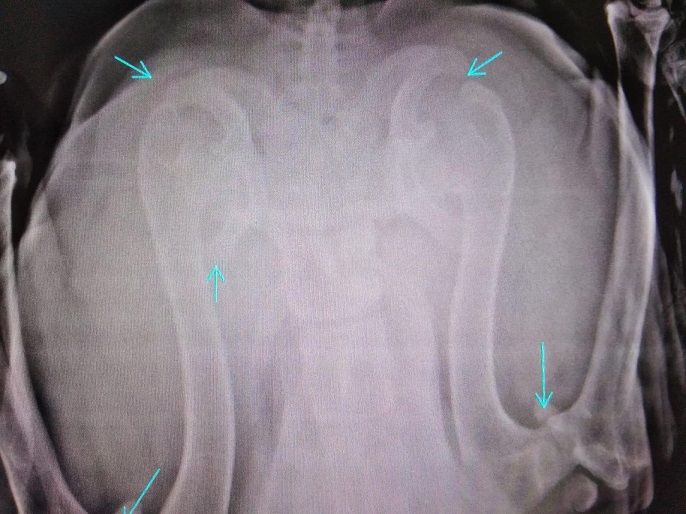

TORIN wurde von Aniela an einer Brücke gefunden, festgebunden mit einem kurzen Stück Kordel. Der super freundliche Kerl war aber quasi nicht im Stande, sich zu bewegen. Beide Hinterläufe konnten nicht richtig benutzt werden, die Knie schienen völlig lädiert zu sein. Schnell war klar, ein Hund wie TORIN (groß, riesen Handicap) wird wenig Chancen haben und kann vor Ort in Rumänien aber auch nicht ausreichend versorgt werden. Der Eulenhof am Niederrhein e.V. hat auch ihn als Gnadenplatzhund aufgenommen und dank seiner tollen Paten geht es nun stetig aufwärts. Neben einer guten Schmerztherapie bekommt TORIN regelmäßige Physiotherapie und kann sich auf dem großen Gelände des Eulehhofs frei bewegen und seine Muskulatur wieder gut aufbauen. Zusätzlich bekommt er sehr viele Zusatzpräparate. All das zusammen hat TORINS Bewegungsablauf massiv verbessert und er kann nun sogar mit anderen Hunden spielen. Er hat wirklich deutlich an Lebensqualität gewonnen und wir freuen uns so sehr, dass ein Notfall wie er diese Chance erhalten hat.